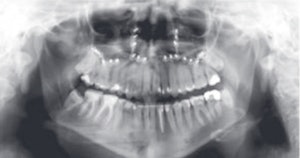

In a session on Sunday, ECR delegates had a chance to learn all about dental imaging. When imaging the head and neck region with CT or MRI, teeth are always present, according to chairperson Dr. Julia Frühwald-Pallamar, an assistant professor in the radiology department at the Medical University of Vienna in Austria. On scans performed for other indications, radiolucent or radiopaque lesions of the jaw can be encountered, and familiarity with typical dental conditions is necessary to decide on the right therapy for patients.

High-resolution (3-tesla) MRI of a patient with an inflammatory endoperiodontal lesion at tooth 017 (arrow). Sagittal T2-weighted space (A), T1-weighted plus gadolinium (B). Images courtesy of Dr. Stefan Rohde.Imaging in these patients is usually performed with 2D panoramic radiography, CT, or CBCT. However, MRI may represent a complementary imaging technique to visualize particular pathological processes, especially inflammatory disease of the periodontal space, or teeth vascularization after trauma, he said. His presentation focused on the potential of high-resolution MRI in this new field and compared it with CT and CBCT.

Dentists may make special use of MRI in difficult situations, for example when conventional imaging fails to detect inflammatory or neoplastic processes at an early stage, because visualization is only possible when resorption of the alveolar bone has already started. In addition, MRI offers an alternative technique especially in younger patients and children to avoid radiation exposure, he added.

T2-weighted (A) and contrast-enhanced T1-weighted images (B) of a patient with a periapical granuloma at tooth 015 (arrow) and odontogenic sinusitis in the maxillary sinus (open arrow). Images courtesy of Dr. Stefan Rohde."MRI of the dental apparatus is technically challenging as the bony structures of the mandible and teeth give only little or no MR signal," Rohde said. "Another concern is the problem of air content and metal artifacts in the oral cavity that limit the use of MRI in this special setting. As a principal finding of our experiments, MRI proved to be superior to MDCT [multidetector-row CT] and to CBCT in visualizing periodontal structures like the periodontal space and the adjacent lamina dura. Surprisingly, even cortical and trabecular bone were displayed better with MRI than with MDCT and CBCT. Therefore, I believe that MRI could become an important complementary imaging source of the jaw and teeth apparatus in pathologies of tissue investing and supporting the teeth."